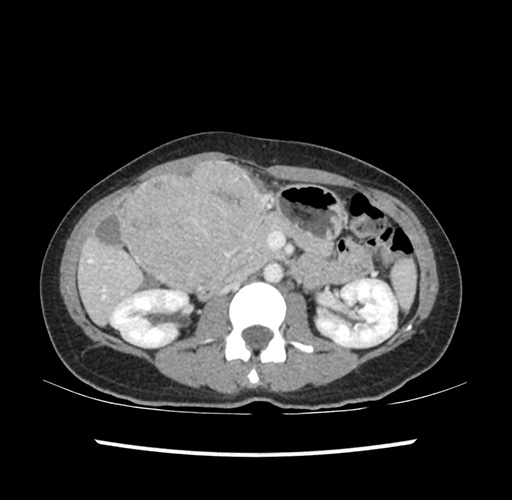

Imaging Analysis

Look through the patient's CT scan to identify any areas of concern for the necessary procedure.

Based on your CT findings, which issue(s) would give reason for "planned slowing down moment(s)" in this case?

Considering a standard left lateral sectionectomy procedure, what step(s) of the operation would you do differently in this case ?